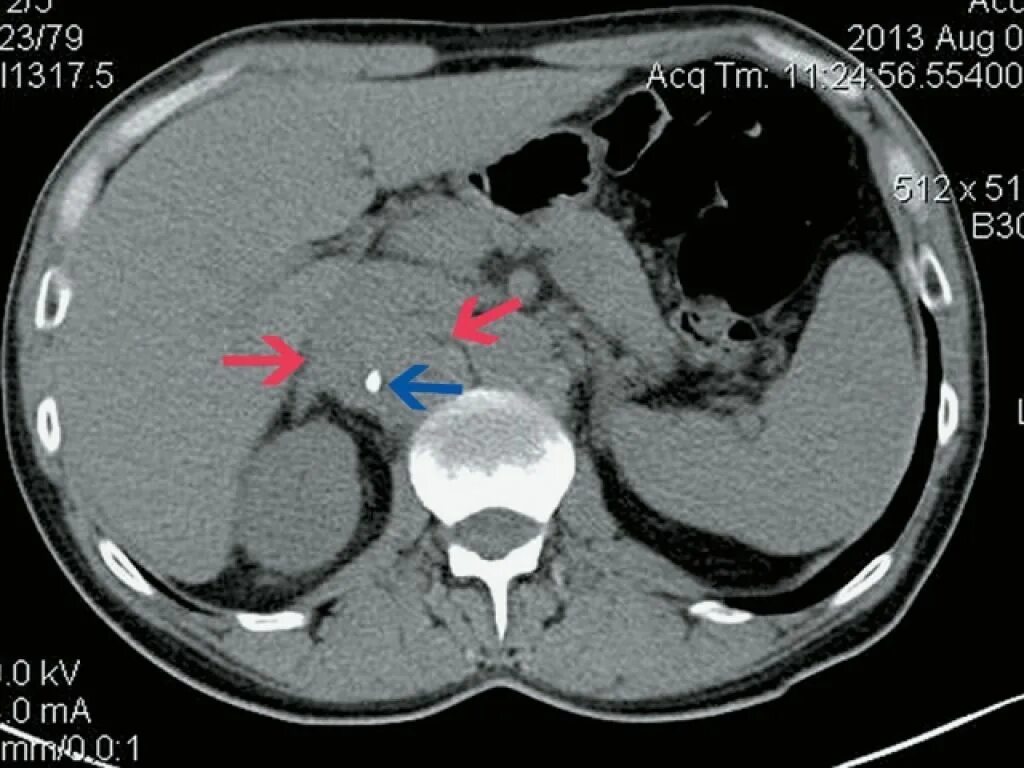

Забрюшинная онкология